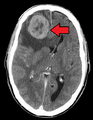

Metastases from the lungs to the brain